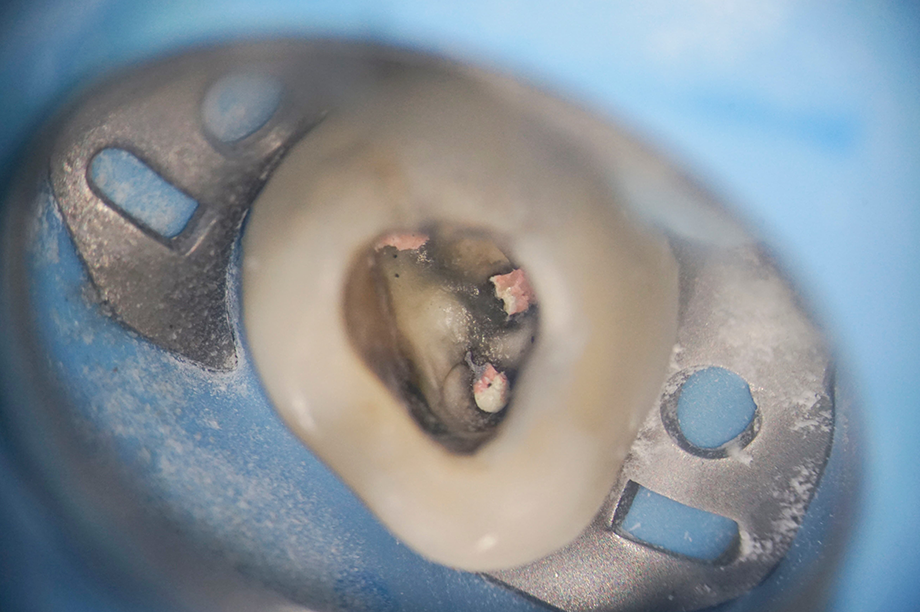

歯の根の中(根管)は暗く、複雑に枝分かれしており、肉眼で中を見通すことは不可能です。

マイクロスコープを用いることで、これまでは手探りで行っていた清掃作業を、根管の奥深くまで直接確認しながら進めることができます。

非常に細い根管や、複雑に湾曲した管の発見

過去の治療で残ってしまった古い充填剤の完全な除去

肉眼では見落としがちな微細な亀裂(破折線)の確認

これまで原因不明とされていた痛みの理由が視覚的に特定できるケースもあり、抜歯を宣告された歯を保存するための可能性を広げることができます。